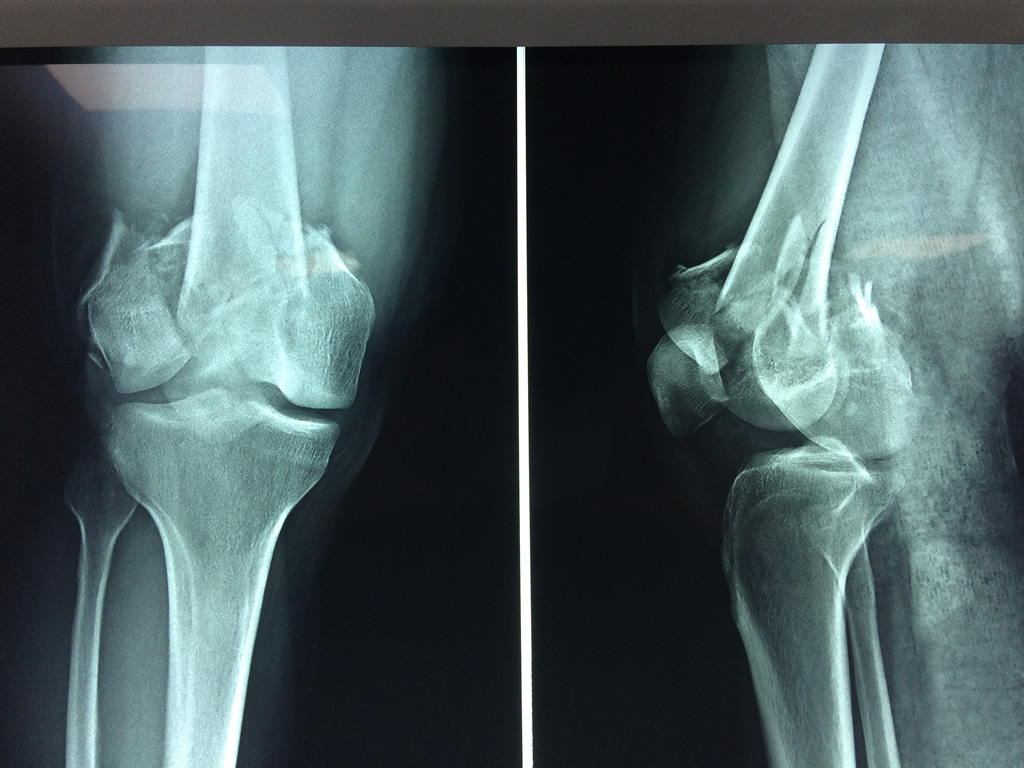

Cirugía de Rodillas